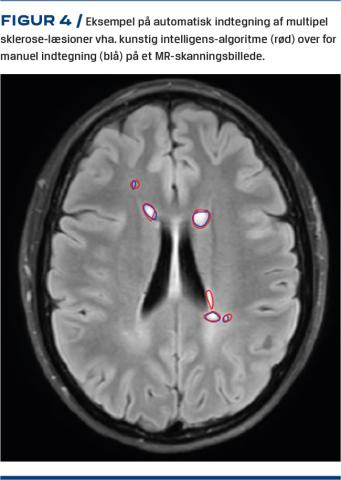

AI som beslutningsstøtte ved klinisk billeddiagnostik er under udvikling mange steder til brug ved mammografi, røntgenoptagelser af thorax samt muskel-og skeletundersøgelser i et stort EU-projekt ledet fra Bispebjerg Hospital. MR-skanning anvendes til udredning og monitorering af multipel sklerose, der manifesterer sig som små hvide læsioner på MR-skanningsbilleder. Antal og volumen af læsioner på MR-skanningsbillederne er centralt for monitorering af patienterne, som følges over år med gentagne skanninger, og man indtegner ofte disse læsioner på billederne – et arbejde, som er langsommeligt og omstændeligt. Mange arbejder med AI til automatisk løsning af denne opgave, men en metode er endnu ikke indført klinisk. Ved den internationale konference Challenge MICCAI 2017 søgte man at lave den bedst mulige algoritme til indtegning af disse læsioner på et kendt dataset [22]. Vi valgte den vindende algoritme [23], og i et masterprojekt fra DTU og KU har civilingeniør Amalie Hindsholm udviklet AI til at matche speciallægers indtegninger [24] (Figur 4). Efter en prospektiv evaluering er målet at indføre metoden som rutine.